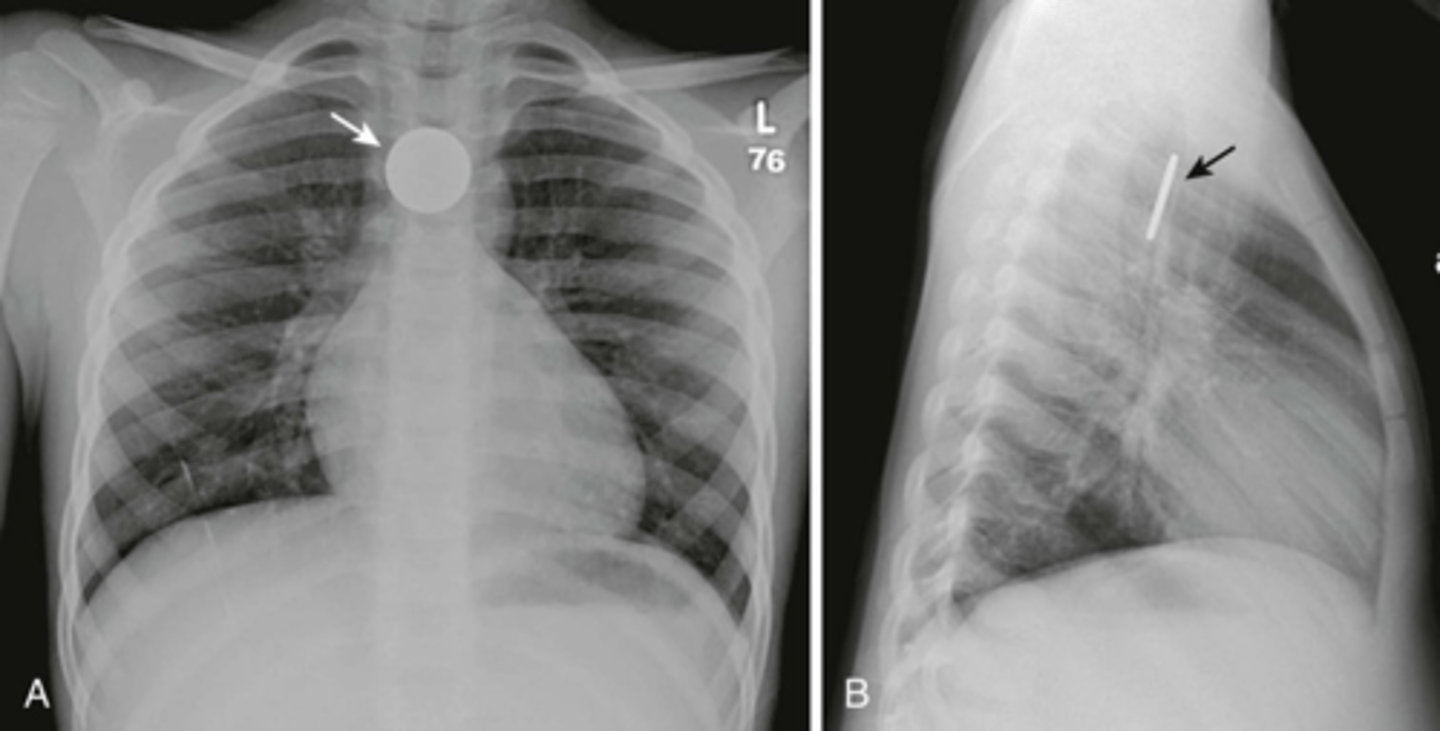

What is a congenital diaphragmatic hernia (CDH), & what is the primary complication of this condition?

Failure of diaphragmatic tissue to close resulting in the abdominal contents to herniate into the thoracic cavity; respiratory insufficiency (herniated intestines interfere w/ lung development)

What are some s/sxs of a CDH?

Respiratory distress, scaphoid abdomen, shift of heart sounds to the right, tachypnea, nasal flaring, cyanosis, bowel sounds or absent breath sounds on affected side

What is the best initial test for a CDH? How is it managed?

Diagnosis: CXR

Treatment: intubation & mechanical ventilation, surgery after 24-48 hrs (delayed to allow for improvement in pulmonary HTN)